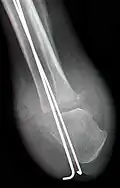

Der operative Zugang für die Amputation erfolgt von vorn (ventral), mit Bildung eines weiter nach distal reichenden Sohlenlappens, der dann den ventralen Defekt decken kann und auch dort eine Endbelastungsfähigkeit herstellt. Die Haut des Fußrückens ist hingegen sehr druckempfindlich und dort, wo durch die Belastung oder die Prothese Druck entsteht, gefährdet. Nach Darstellung des Sprungbeins wird dieses komplett entfernt (Astragalektomie). Die Gelenkfläche des oberen Sprunggelenks wird zusammen mit Innen- und Außenknöchel durch eine horizontale Osteotomie mit einer oszillierenden Säge reseziert, unter besonders sorgfältiger Schonung der hinter dem Innenknöchel verlaufenden Gefäße. Anschließend erfolgt auch am Fersenbein eine horizontale Osteotomie, wodurch alle Gelenkanteile des subtalaren Gelenkes entfernt werden. Durch die Entfernung des Sprungbeins werden etwa 3 bis 4 cm Platz gewonnen, sodass auch eine starke Achillessehnenverkürzung hierdurch in der Regel bereits ausgeglichen ist und eine Sehnenverlängerung selten notwendig ist. Die Entfernung der Malleolen erfolgt für eine gute Prothesenversorgung. Die calcaneotibiale Arthrodese erfolgt unter Kompression und mit einem Vorschub des Fersenbeins um etwa 10 bis 15 mm, wobei das Fersenbein in einer leichten Außendrehung wie auf der Gegenseite eingestellt werden muss. Anschließend ist eine Abrundung der distal-plantaren Fersenbeinkante vor allem an der Außenseite notwendig, um keine druckempfindliche knöcherne Prominenz zu erzeugen. Als Osteosynthese wird meist ein Fixateur externe mit jeweils zwei Steinmann-Nägeln oder langen Schrauben in Tibia und Calcaneus eingesetzt, alternativ gekreuzte K-Drähte, die von proximal durch Tibia und Calcaneus eingeführt werden und dadurch die Sohlenhaut nicht verletzen. Ein Hautschluss muss spannungsfrei erfolgen.[1]

Durch die feste Fixierung mittels Drähten, Schrauben oder Fixateur externe ist nach Abschwellen und Wundheilung eine umgehende Belastung des Stumpfes möglich, und eine Prothesenversorgung erfolgt nach vollständigem Rückgang des postoperativen Ödems und der Materialentfernung nach etwa sechs Wochen.